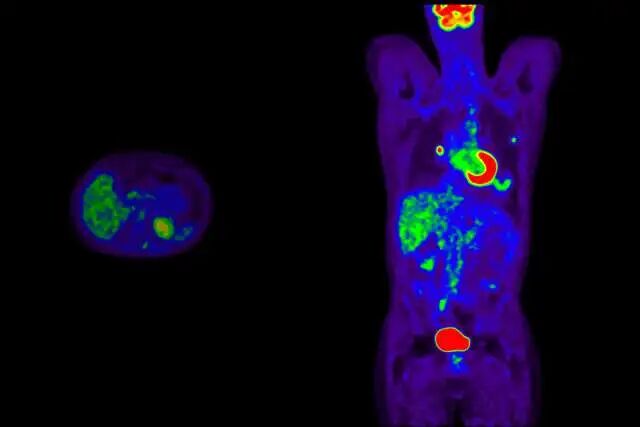

未来医学:全美首个核医学与诊疗一体化系

2026 年 1 月 1 日,UCLA Health 正式成立核医学与诊疗一体化系(Nuclear Medicine & Theranostics),成为全美首个独立成系的此类部门。

这一模式致力于缩短从”实验室”到”病房”的距离。通过放射性药物,实现”发现即治疗”——既能精准定位疾病,又能直接实施靶向打击,为复杂与疑难疾病带来新的希望。